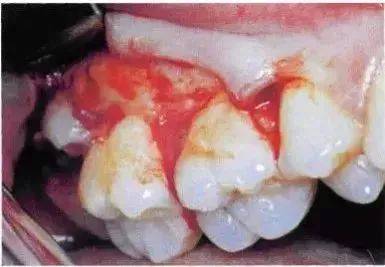

该病例也可以不切割牙冠而拔除。拔牙时,去除了牙根间隔。